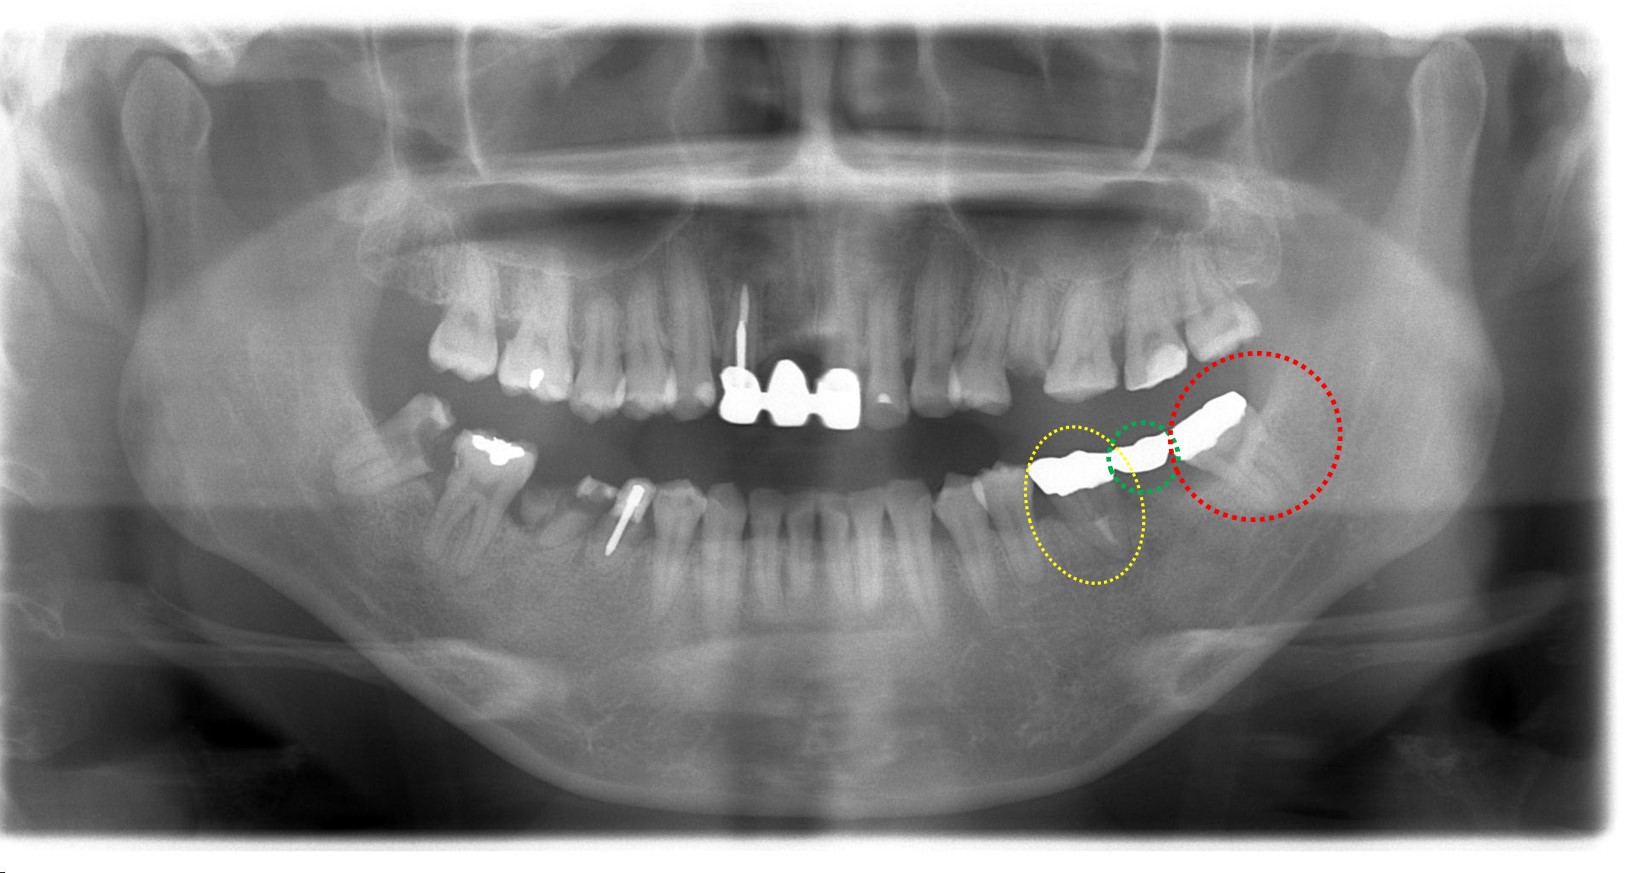

左写真が術前、真ん中が移植3ヶ月後のブリッジが入る前の状態、右写真はブリッジ装着後の写真になります。

青〇の歯は抜歯して代わりに親知らずが引っ越してきました。